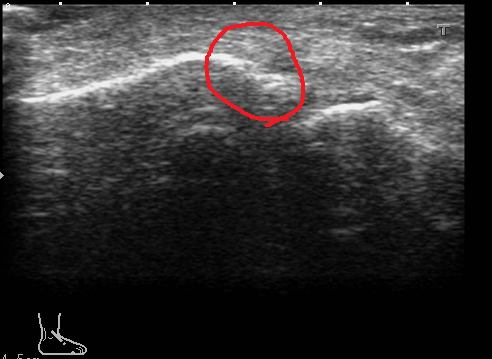

足をひねり来院されました。 捻挫を疑い超音波で診察しました。

やはり前距腓靭帯(赤い部分の間の黒い部分)に損傷(断裂)があり、固定を致しました。